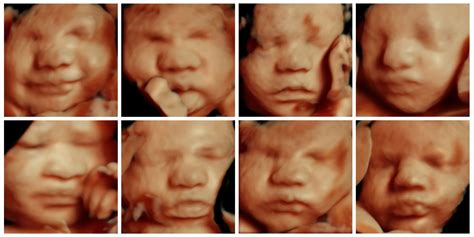

What Is A 4D Ultrasound Scan? Importance And How It Works, 40% OFF